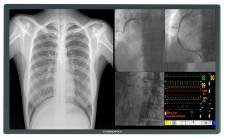

4K 8MP HD Cath Lab Display Monitor Screen

Instead of making use of four to six displays, many are instead opting to update their displays with one large UHD 4K display. When a UHD display is combined with a video manager, it has the ability to become customizable with a variety of layout options and editing tools like magnification. The design is easier to use and provides a higher resolution, making its adoption an easy choice as it facilitates precise procedures and minimally invasive surgeries.

The pending patent Hybridpixx touts an ingenious design that garners all the advantages of 4K UHD display, while mitigating the dangers associated with a single large display. The mount holds two 58 inch displays in place, so if the primary display fails, a back-up display with exactly the same parameters is ready. With a modular connection, the wireless display can be easily switched in under a minute.

Available in 58 inches, the 4K UHD monitor can be employed in both analog and digital cath labs. With the option to purchase our video manager, all the benefits of customizable layouts and modification are possible as well. Additionally, it can be utilized in a variety of spaces, including hybrid operating rooms that facilitate both surgical and interventional procedures.